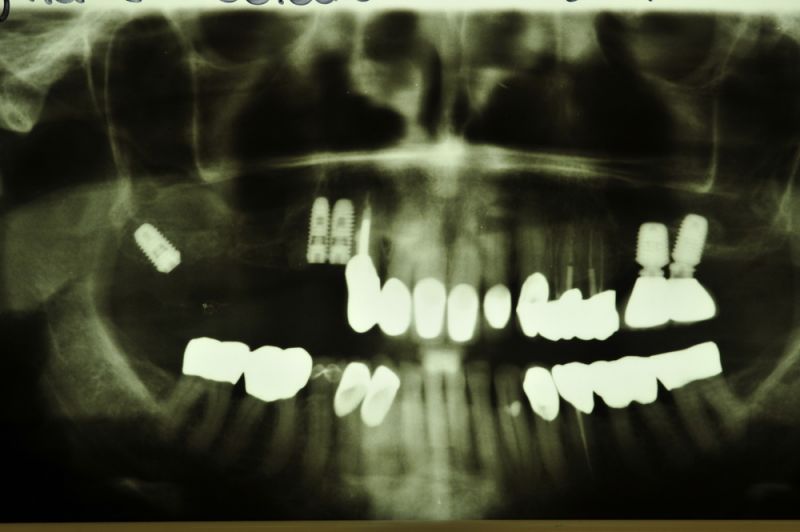

Kieler Patientin zur Freilegung von drei Implantaten im Oberkiefer

Die Insertion der drei Implantate im ersten Quadranten stellte sich knochenbedingt etwas anders dar, als sonst üblich.

Das eigentlich für den Bereich 17 geplante Implantat wurde in einer starken Winkelung in den ortsständigen Knochen 18 inseriert.

Was bei Zähnen nicht geht, ist bei Implantaten problemlkos möglich. Eine nichtzahnachsengerechte Schrägbelastung.

Die Erfahrung zeigt, dass es besser ist ein Implantat schräg in ortsständigen Knochen zu inserieren, als ein Implantat gerade in einen augmentierten Knochen einzubringen, weil der körpereigene, ortsständige Knochen wesentlich widerstandsfähiger ist, als der künstlich angezüchtete augmentierte Knochen.